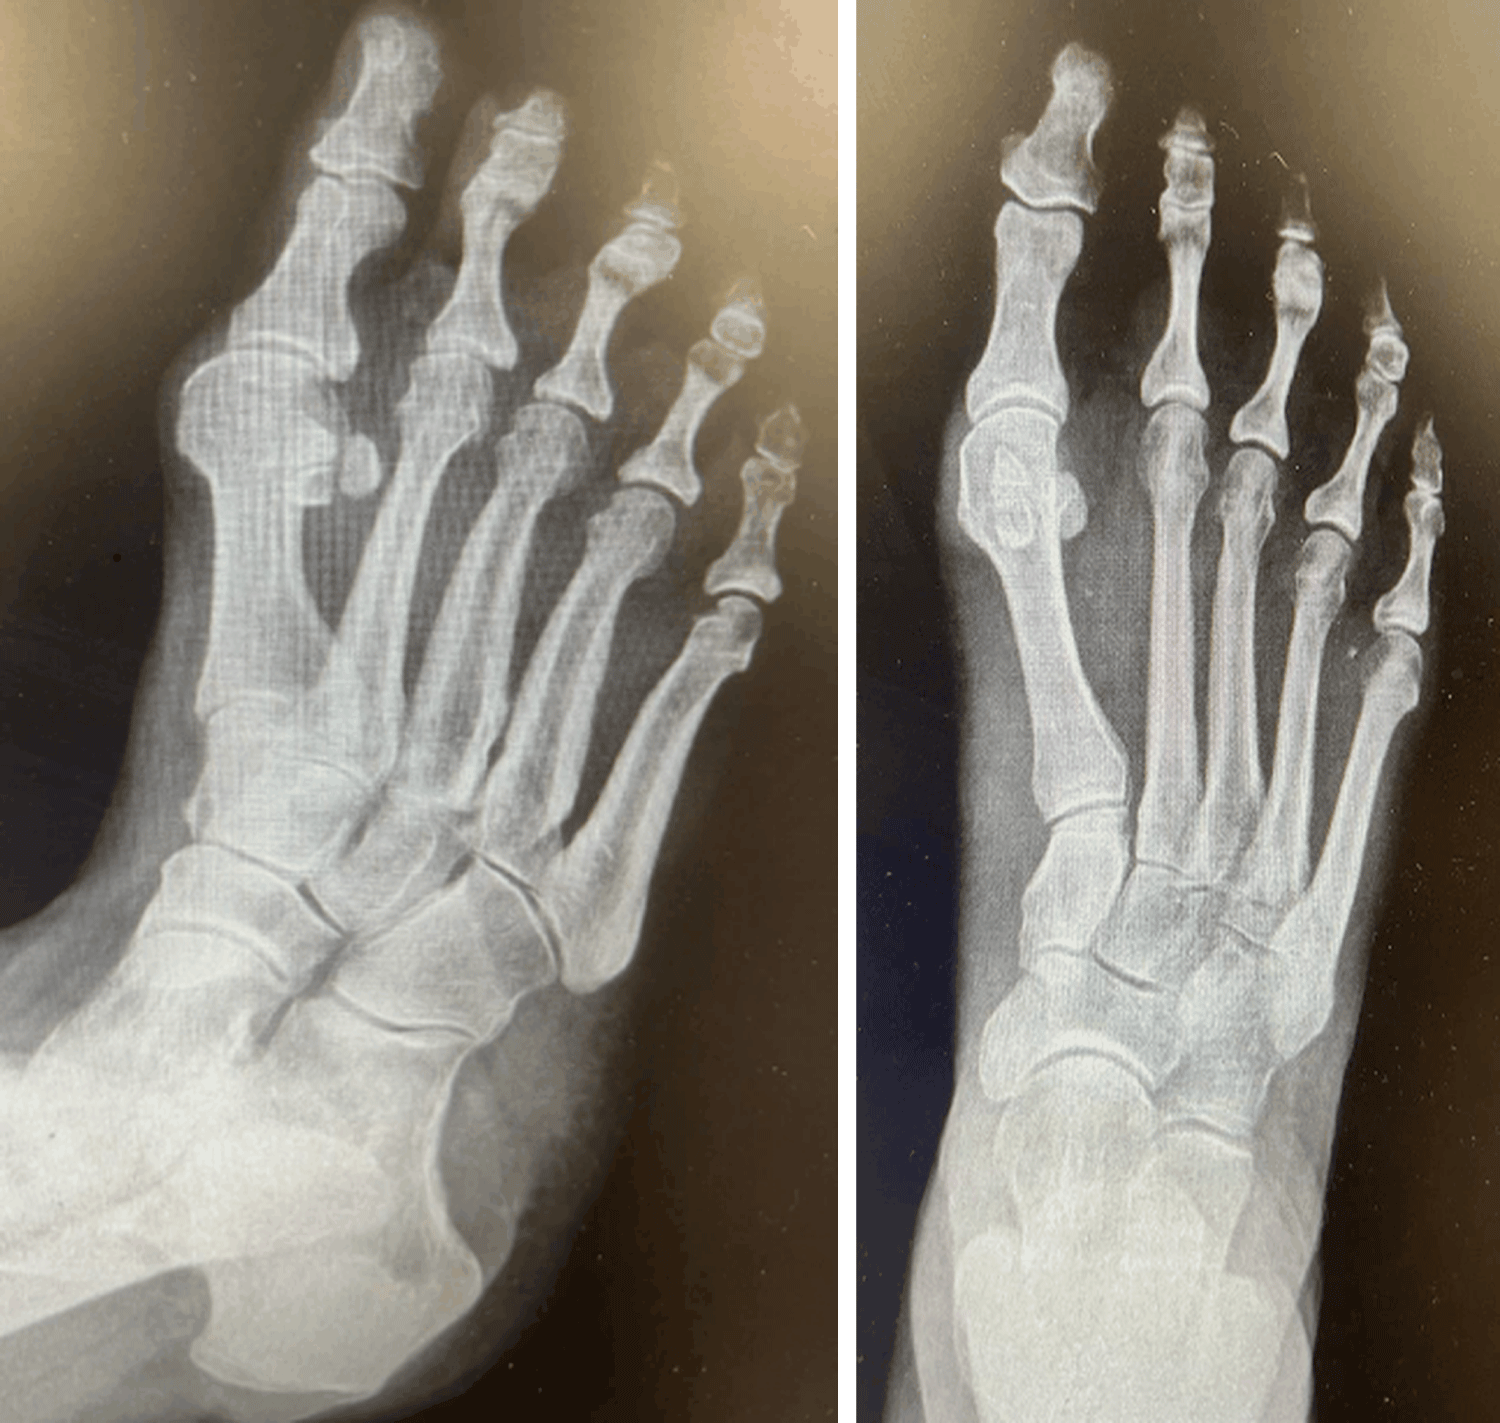

A three-view radiographic examination of the right foot was essentially unremarkable (Figure 1). It showed no evidence of intralesional mineralization, osseous erosion, or remodeling of the metatarsal bones. Afterwards, a magnetic resonance imaging (MRI) of the right foot was conducted revealing a subcutaneous lesion between the distal 1 st and 2 nd metatarsal (Figure 2).

Figure 1: Anteroposterior view of right foot X-ray. View Figure 1